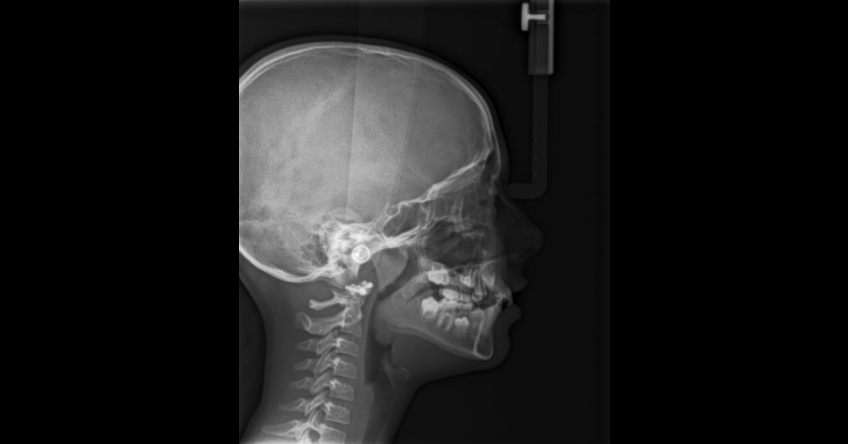

Let’s look at the three most common causes of compromised craniofacial anatomy and patient care.

If the issue is genetic, my recommendation is to immediately begin dentistry to redirect the growth to a more positive pattern. The problem I’ve run into is the belief in the orthodontic community that you can wait and treat during a growth spurt and you’ll the same result as treating early. While I find significant flaws in the historical literature supporting that view, I won’t argue the point here. The important thing to understand is that orthodontics in these patients is no longer about smiles and function.

The advantage to early intervention is improving brain and body health. The contemporary literature is replete with studies showing that children suffer when we choose to not intervene. Most don’t grow out of these problems; they tend to grow into them. Dentistry must move beyond the mechanical nature of our profession and recognize the powerful tools we must use to change lives by improving breathing and sleep.

Breathing against resistance caused by large lymphoid tissues

If the child is breathing against the resistance offered by the tonsils and adenoids, they will grow abnormally, whether a little or a lot. Therefore, any child receiving AT should have orthodontic treatment to help normalize their growth. If you can’t get the tissue removed surgically, the child’s abnormal growth pattern will continue until breathing is normalized (nasal breathing).